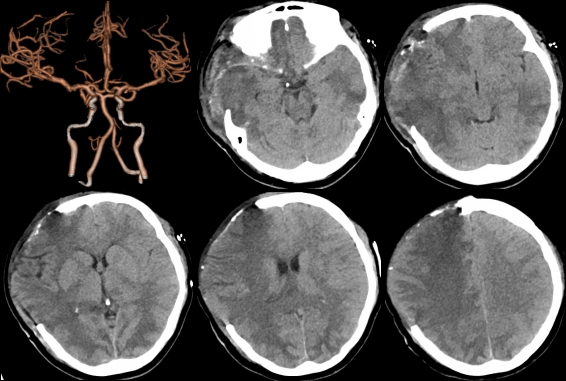

接诊的文荣主治医师仔细查看患者的影像检查资料,结合病史,考虑脑梗塞。完善相关检查后,头部CTA提示双侧大脑出现广泛可疑梗塞灶,脑中线明显左偏,脑干受压,右侧大脑中动脉显影不连续,产褥期的女性,血液处于高凝状态,不排除血栓可能。

术前脑CTA发现右侧大脑中动脉连续中断,右侧脑组织内大量低密度影

术后头部CTA示中线移位和脑干受压得到缓解,右侧大脑中动脉显影连续

手术后神经外科和重症医学科医护人员多次对该患者病情进行了讨论,调整治疗方案,早期予以抗凝治疗,头部CTA示中线移位和脑干受压得到缓解,右侧大脑中动脉显影连续。手术一周后,在大家的精心照顾下,L女士已经苏醒,一家三口终得团聚。